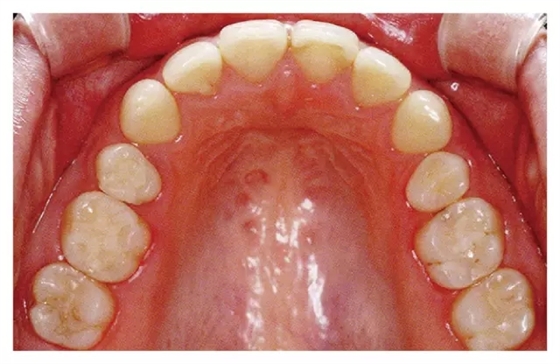

規(guī)格照片拍攝基準(zhǔn)

◇將大小調(diào)整至前牙到最后一顆臼齒均能看清

◇將牙齒正中部位放置于照片的中心位置

◇對(duì)焦在65·56牙齒附近。 拍攝時(shí)的注意點(diǎn)

◇調(diào)節(jié)反光鏡位置,使咬合面盡量能從正上方拍攝

◇對(duì)口腔進(jìn)行空氣干燥處理

① 使用咬合面專用鏡

② 在7·7牙的遠(yuǎn)心處插入反光鏡下端

① 選用比牙弓更大一些的咬合面專用鏡

② 反光鏡的下端放置在使得上頜最里面的臼齒后面還稍有空隙的位置

③ 在54·45牙齒附近放置兩個(gè)較小的開口器

① 開口器朝上拉起使上唇鼓起

② 將反光鏡的上端略朝下頜方向傾斜。注意反光鏡背面不要弄到下唇